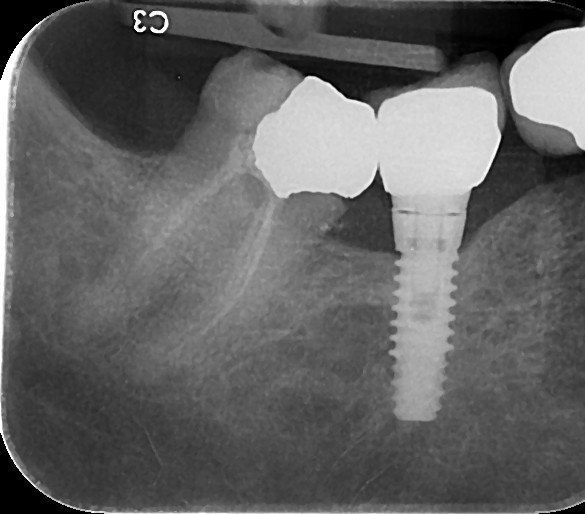

1. What option can be selected regarding the implant seen in this X ray?